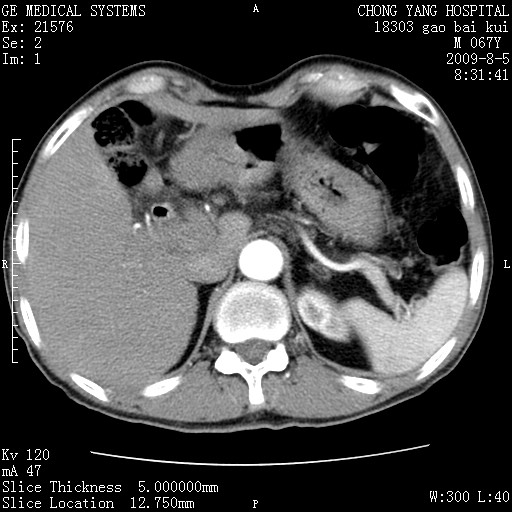

这个也过了,考虑胰腺钩突癌或壶腹癌,不除外胰管粘液乳头瘤伴胰管扩张,肝内胆管积气.

1)考虑胰头癌或壶腹癌并胰管扩张。2)肝外胆管扩张、积气,胆囊影未见;考虑术后改变。3)胃壁增厚?建议必要时行胃镜检查。

虑胰腺钩突癌或壶腹癌,不除外胰管粘液乳头瘤伴胰管扩张,肝内胆管积气.

考虑胰头癌并十二指肠受侵。